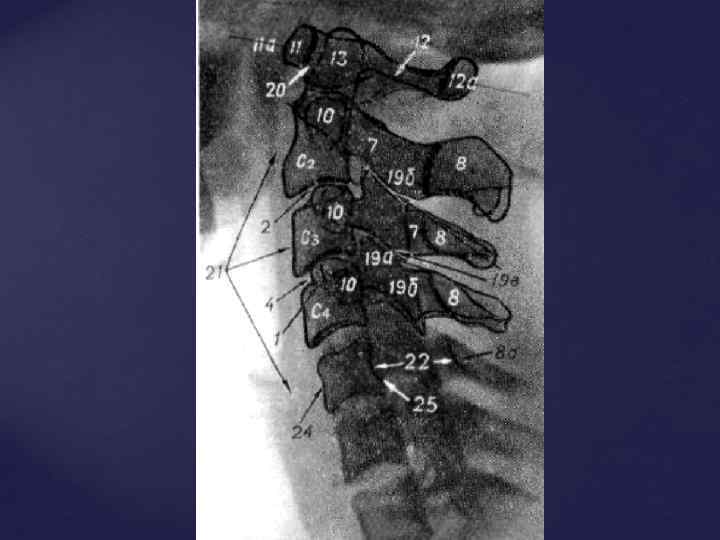

СРОКИ ОКОСТЕНЕНИЯ КОСТЕЙ ЧЕЛОВЕКА 1. ПОЗВОНОЧНИК - появление трех точек окостенения (т. о. ) (тело и две половины дуги) - внутриутробно - синостоз дуги и тела – 2 -3 года - синостоз обеих половин дуг – 1 -8 лет (в зависимости от уровня) - появление добавочных т. о. (апофизы - лимбы позвонков) – 7 -8 лет - полное слияние всех добавочных т. о. - 23 -26 лет - синостозирование крестца – 11 -12 лет

СРОКИ ОКОСТЕНЕНИЯ КОСТЕЙ ЧЕЛОВЕКА 1. ПОЗВОНОЧНИК - появление трех точек окостенения (т. о. ) (тело и две половины дуги) - внутриутробно - синостоз дуги и тела – 2 -3 года - синостоз обеих половин дуг – 1 -8 лет (в зависимости от уровня) - появление добавочных т. о. (апофизы - лимбы позвонков) – 7 -8 лет - полное слияние всех добавочных т. о. - 23 -26 лет - синостозирование крестца – 11 -12 лет